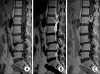

Methods: The spinal IDEM tumor patients (11 cases) who had been treated by surgical excision and who were followed up more than 1 year were retrospectively analyzed. Pain was evaluated by the visual analogue scale (VAS) and the neurologic function was assessed by Nurick's grade. The pathological diagnosis, the preoperative symptom duration, the tumor location on the sagittal and axial planes and the percentage of tumor occupying the intradural space were investigated. In addition, all these factors were analyzed in relation to the degree of the preoperative symptoms and the prognosis. On the last follow-up, the MRI was checked to evaluate whether or not the tumor had recurred.

Results: The most common diagnosis was schwannomas (73%), followed by meningiomas (18%). The percentage of tumor occupying the intradural space was 82.9 +/- 9.4%. The VAS score was reduced in all cases from 8.0 +/- 1.2 to 1.2 +/- 0.8 (p = 0.003) and the Nurick's grade was improved in all cases from 3.0 +/- 1.3 to 1.0 +/- 0.0 (p = 0.005). The preoperative symptoms were correlated with only the percentage of tumor occupying the intradural space (VAS; r(2) = 0.75, p = 0.010, Nurick's grade; r(2) = 0.69, p = 0.019). One case of schwannoma recurred.

Conclusions: The degree of neurologic symptoms was correlated with the percentage of tumor occupying the intradural space. All the tumors were able to be excised through the posterior approach. The postoperative neurologic recovery was excellent in all the cases regardless of any condition. Therefore, aggressive surgical excision is recommended even for cases with a long duration of symptoms or a severe neurologic deficit.